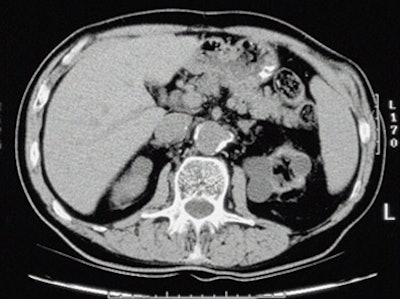

| Top to bottom: Indented kidneys with cysts typical of ESRD, but not 'SICK,' seen in a 61-year-old patient. All patients were imaged within three months of ESRD diagnosis and the beginning of dialysis, and yielded only subtle CT findings in most of them. All images courtesy of Lauren Brubaker. |

"We developed the acronym 'SICK' to indicate bilaterally small, indented, and calcified kidneys," she said. "In terms of radiological findings, as you would expect, we found small, smooth kidneys in 65% of our ESRD population. Other typical ESRD patterns were small kidneys with cysts, as well as kidneys with so many cysts they are causing indentations or scars within the kidneys. Contour was assessed for calcification through scars, as well as calcifications for size and location."